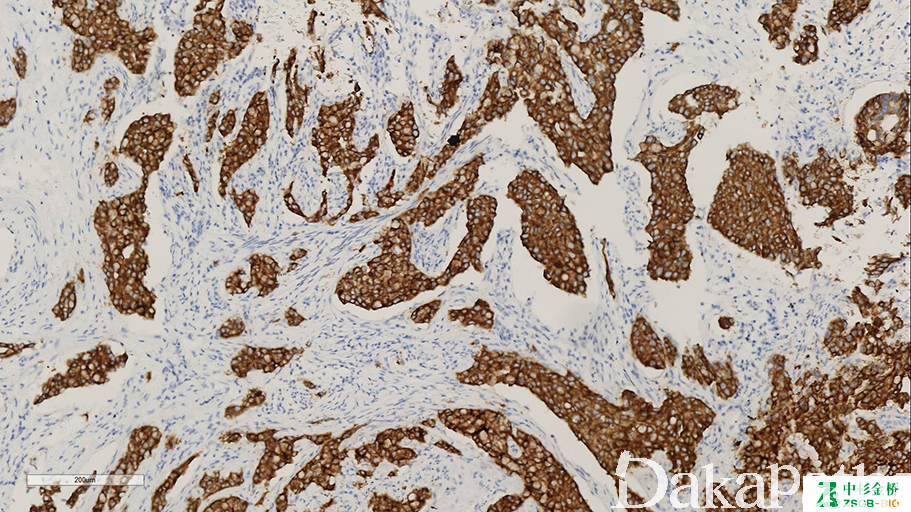

为一种酪氨酸激酶受体,第 2 号染色体上的 ALK 基因可与多种基因发生融合,不同融合方式可导致阳性信号信号分布不同,信号强度与修复缓冲液不同有关。

信号定位: 胞浆、胞膜、核膜和胞核均可,方式包括膜+浆、浆+核、胞浆点状阳等。

间变性大细胞淋巴瘤及炎性肌纤维母细胞瘤的诊断与鉴别诊断,约 1/2—2/3 的炎性肌纤维母细胞瘤核膜阳性;